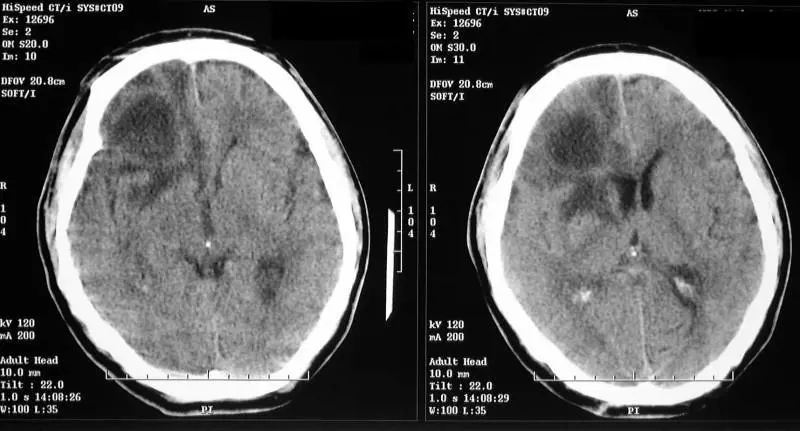

E' in stato vegetativo dal 2003, a causa di un incidente stradale che lo ha inchiodato al letto per tutti questi anni. Ma il giovane 29enne al centro di uno studio che ha guadagnato le pagine del New England Journal of Medicine si è mostrato capace di "comunicare" con i medici, rispondendo sì o no alle domande che gli venivano poste dai camici bianchi. Come? Accendendo quelle aree cerebrali che si attivano nel nostro cervello quando diamo risposte affermative o negative a un quesito.

La ricerca di Adrian Owen La ricerca, condotta da una squadra di studiosi belgi e britannici capitanati da Adrian Owen, del Medical Research Council di Cambridge, a detta degli scienziati potrebbe rivoluzionare il rapporto con questi pazienti, lasciando, ad esempio, che siano loro stessi a esprimersi circa la possibilità di continuare a vivere in quelle condizioni. "Potranno essere coinvolti - ipotizza lo stesso Owen - nelle decisioni relative al loro destino". Grazie a uno scanner di ultima generazione, gli studiosi hanno "fotografato" l’attività cerebrale del giovane sottoponendogli alcune domande, ad esempio "Tuo padre si chiama Thomas?". Ebbene, nel ragazzo si attivano le stesse aree del cervello che si accendono nelle persone sane.

I risultati dei test "Siamo rimasti attoniti - riconosce Owen sulle pagine del britannico Daily Mail - quando abbiamo visto i risultati dei test, che mostravano chiaramente che l’uomo era in grado di rispondere alle nostre domande. Non solo i risultati dello scanner ci dimostravano che il paziente non era in uno stato vegetativo, ma per la prima volta in tanti anni ci consentivano di vedere che l’uomo riusciva a comunicare col mondo esterno".